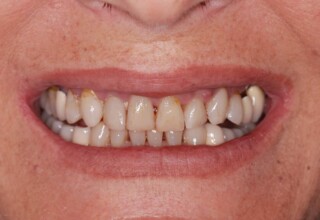

Porcelain Veneers

The best way to solve esthetic problems of the anterior teeth. They combine very little tooth grinding with very high esthetic performance. In the following extensive case anterior teeth presented with: old restorations, staining, poor shape, length and tooth –gingiva ratio. Meticulous diagnostic waxing was performed on study casts and temporary veneers were manufactured. Temporary veneers were used intraorally to evaluate the incorporated changes and to further modify and adjust were needed. When esthetics and function were approved by the patient and were satisfying for the operator the temporaries were used as a guide for the final porcelain veneers. The five final veneers on the upper anterior teeth restored the smile of the patient to almost perfection.

Initial appearance

Final appearance